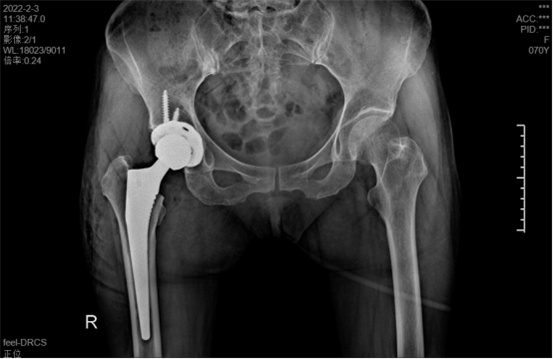

據(jù)羅軍主任介紹,他們首先將鄭阿姨的術(shù)前CT數(shù)據(jù)導(dǎo)入到系統(tǒng)中,通過自動(dòng)識(shí)別骨盆和股骨建立了計(jì)算機(jī)數(shù)字三維模型。AI HIP顯示患者適合使用合適的髖臼杯、股骨柄、標(biāo)準(zhǔn)陶瓷球頭、陶瓷內(nèi)襯,并精準(zhǔn)定位了截骨線,有效幫助醫(yī)生在手術(shù)中做到精確截骨。

在完善相關(guān)檢查充分評(píng)估患者身體情況及手術(shù)風(fēng)險(xiǎn)后,羅軍主任改變傳統(tǒng)手術(shù)方式,在易觀俊主治醫(yī)師、柴重喜醫(yī)師等助手的配合下,為鄭阿姨實(shí)施了人工智能規(guī)劃輔助DAA入路全髖關(guān)節(jié)置換術(shù)。

術(shù)中假體植入和術(shù)前規(guī)劃完全一致

術(shù)中,醫(yī)生在患者髂前上棘外側(cè)切開約8cm長(zhǎng)的切口,小心翼翼地利用闊筋膜張肌與縫匠肌之間的間隙露出髖關(guān)節(jié)。經(jīng)過一番精細(xì)、高難度的操作,成功植入人工髖關(guān)節(jié)組件,以取代受損的股骨頭和髖臼。由于手術(shù)切口小,肌肉組織未受損,鄭阿姨恢復(fù)很快,術(shù)后第1天就能下床活動(dòng)。